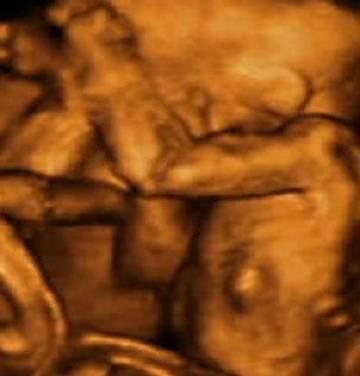

第四张和五张图片中宝宝进一步发育,已经长好了身子和四肢。

接下来的几张图片中,可以看到宝宝基本已经在妈妈肚子中发育完全,可以清楚的观察到宝宝的手指、胳膊、五官,甚至可以在第八张图片中看到宝宝微睁开的双眼和翘起的嘴角。